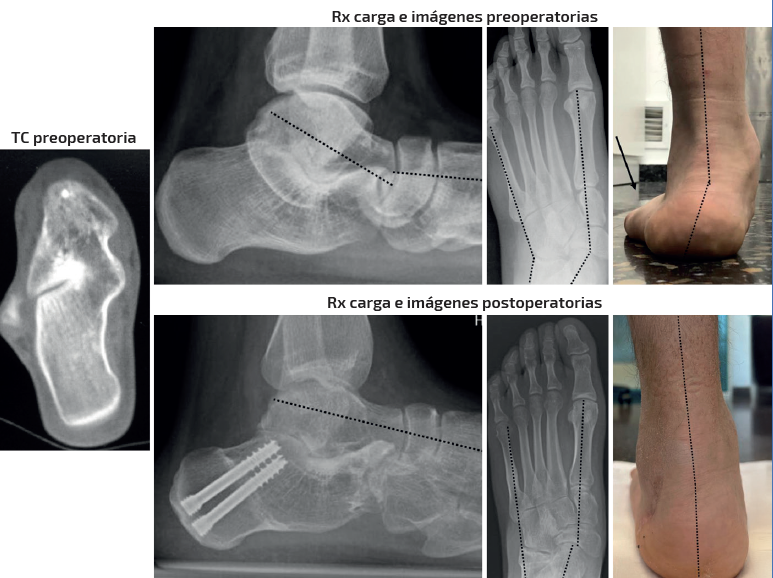

Caso 3 (Figura 6)

Se trata de una paciente mujer de 15 años. Afecta de coalición talocalcánea fibrocartilaginosa con deformidad en plano, valgo y abducto con subtalar rígida. Dolor medial y en sinus tarsi. Tipo IB de Myerson. Tratamiento: doble osteotomía (alargamiento de la columna externa + deslizamiento medial) en el calcáneo y osteotomía pronadora según Cotton + alargamiento del tríceps sural de tipo Strayer. Aloinjerto liofilizado de cresta. Seguimiento: 1,5 años. Mejoría de la alineación clínica y del dolor preoperatorio. Obsérvese cómo en este caso el astrágalo mantiene su flexión plantar en la radiografía lateral pero se ha corregido el abducto y el valgo clínicamente y en la radiografía dorsoplantar. También ha mejorado la altura del arco clínica y en la radiografía anteroposterior (AP) de tobillo (aumento de la altura de la interlínea del tobillo comparativa entre ambos tobillos pre- y postoperatoriamente).